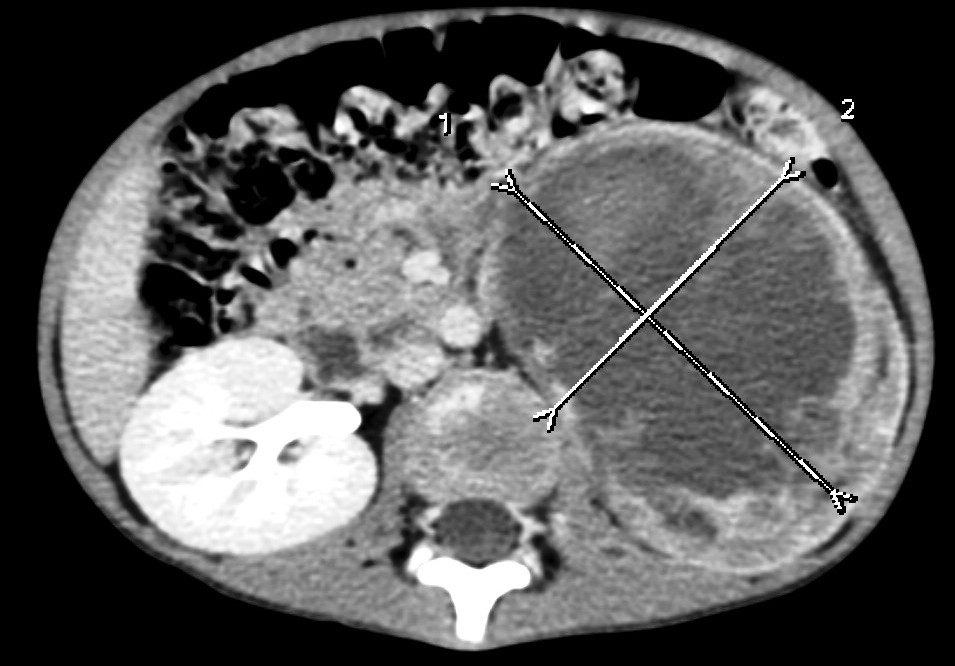

Wilms tumor. It is the most common kidney tumor in childhood that appears between 2-5 years of age. It is usually only noted when the tumor is palpable as an abdominal mass. Hematuria, hypertension, vomiting and abdominal pain are also part of the clinical picture. US examination is a basic method in both the diagnostics and the follow-up of the tumor. The tumor is normally seen as a homogenous or an inhomogeneous mass, dislocating the pyelon and the surrounding retroperitoneal blood vessels. It is important to rule out any lesion in the other kidney. MRI examination: gives a picture of the entire abdomen, kidneys included. Nodal metastases, tumor thrombus are well depictable. CT-examination: is to be chosen if MRI is not available. The tumor shows an inhomogeneous contrast enhancement and pulmonary metastases (invisible to x-ray examination) are also depictable.

Image

27. A solid, echogenic mass arising from the right kidney. Wilms tumor. Abdominal US.

29. CT-examination after iv. contrast administration. Mostly hypodense mass arising from the left kidney. Wilms tumor. (with the courtesy of Dr. Z. Karádi)